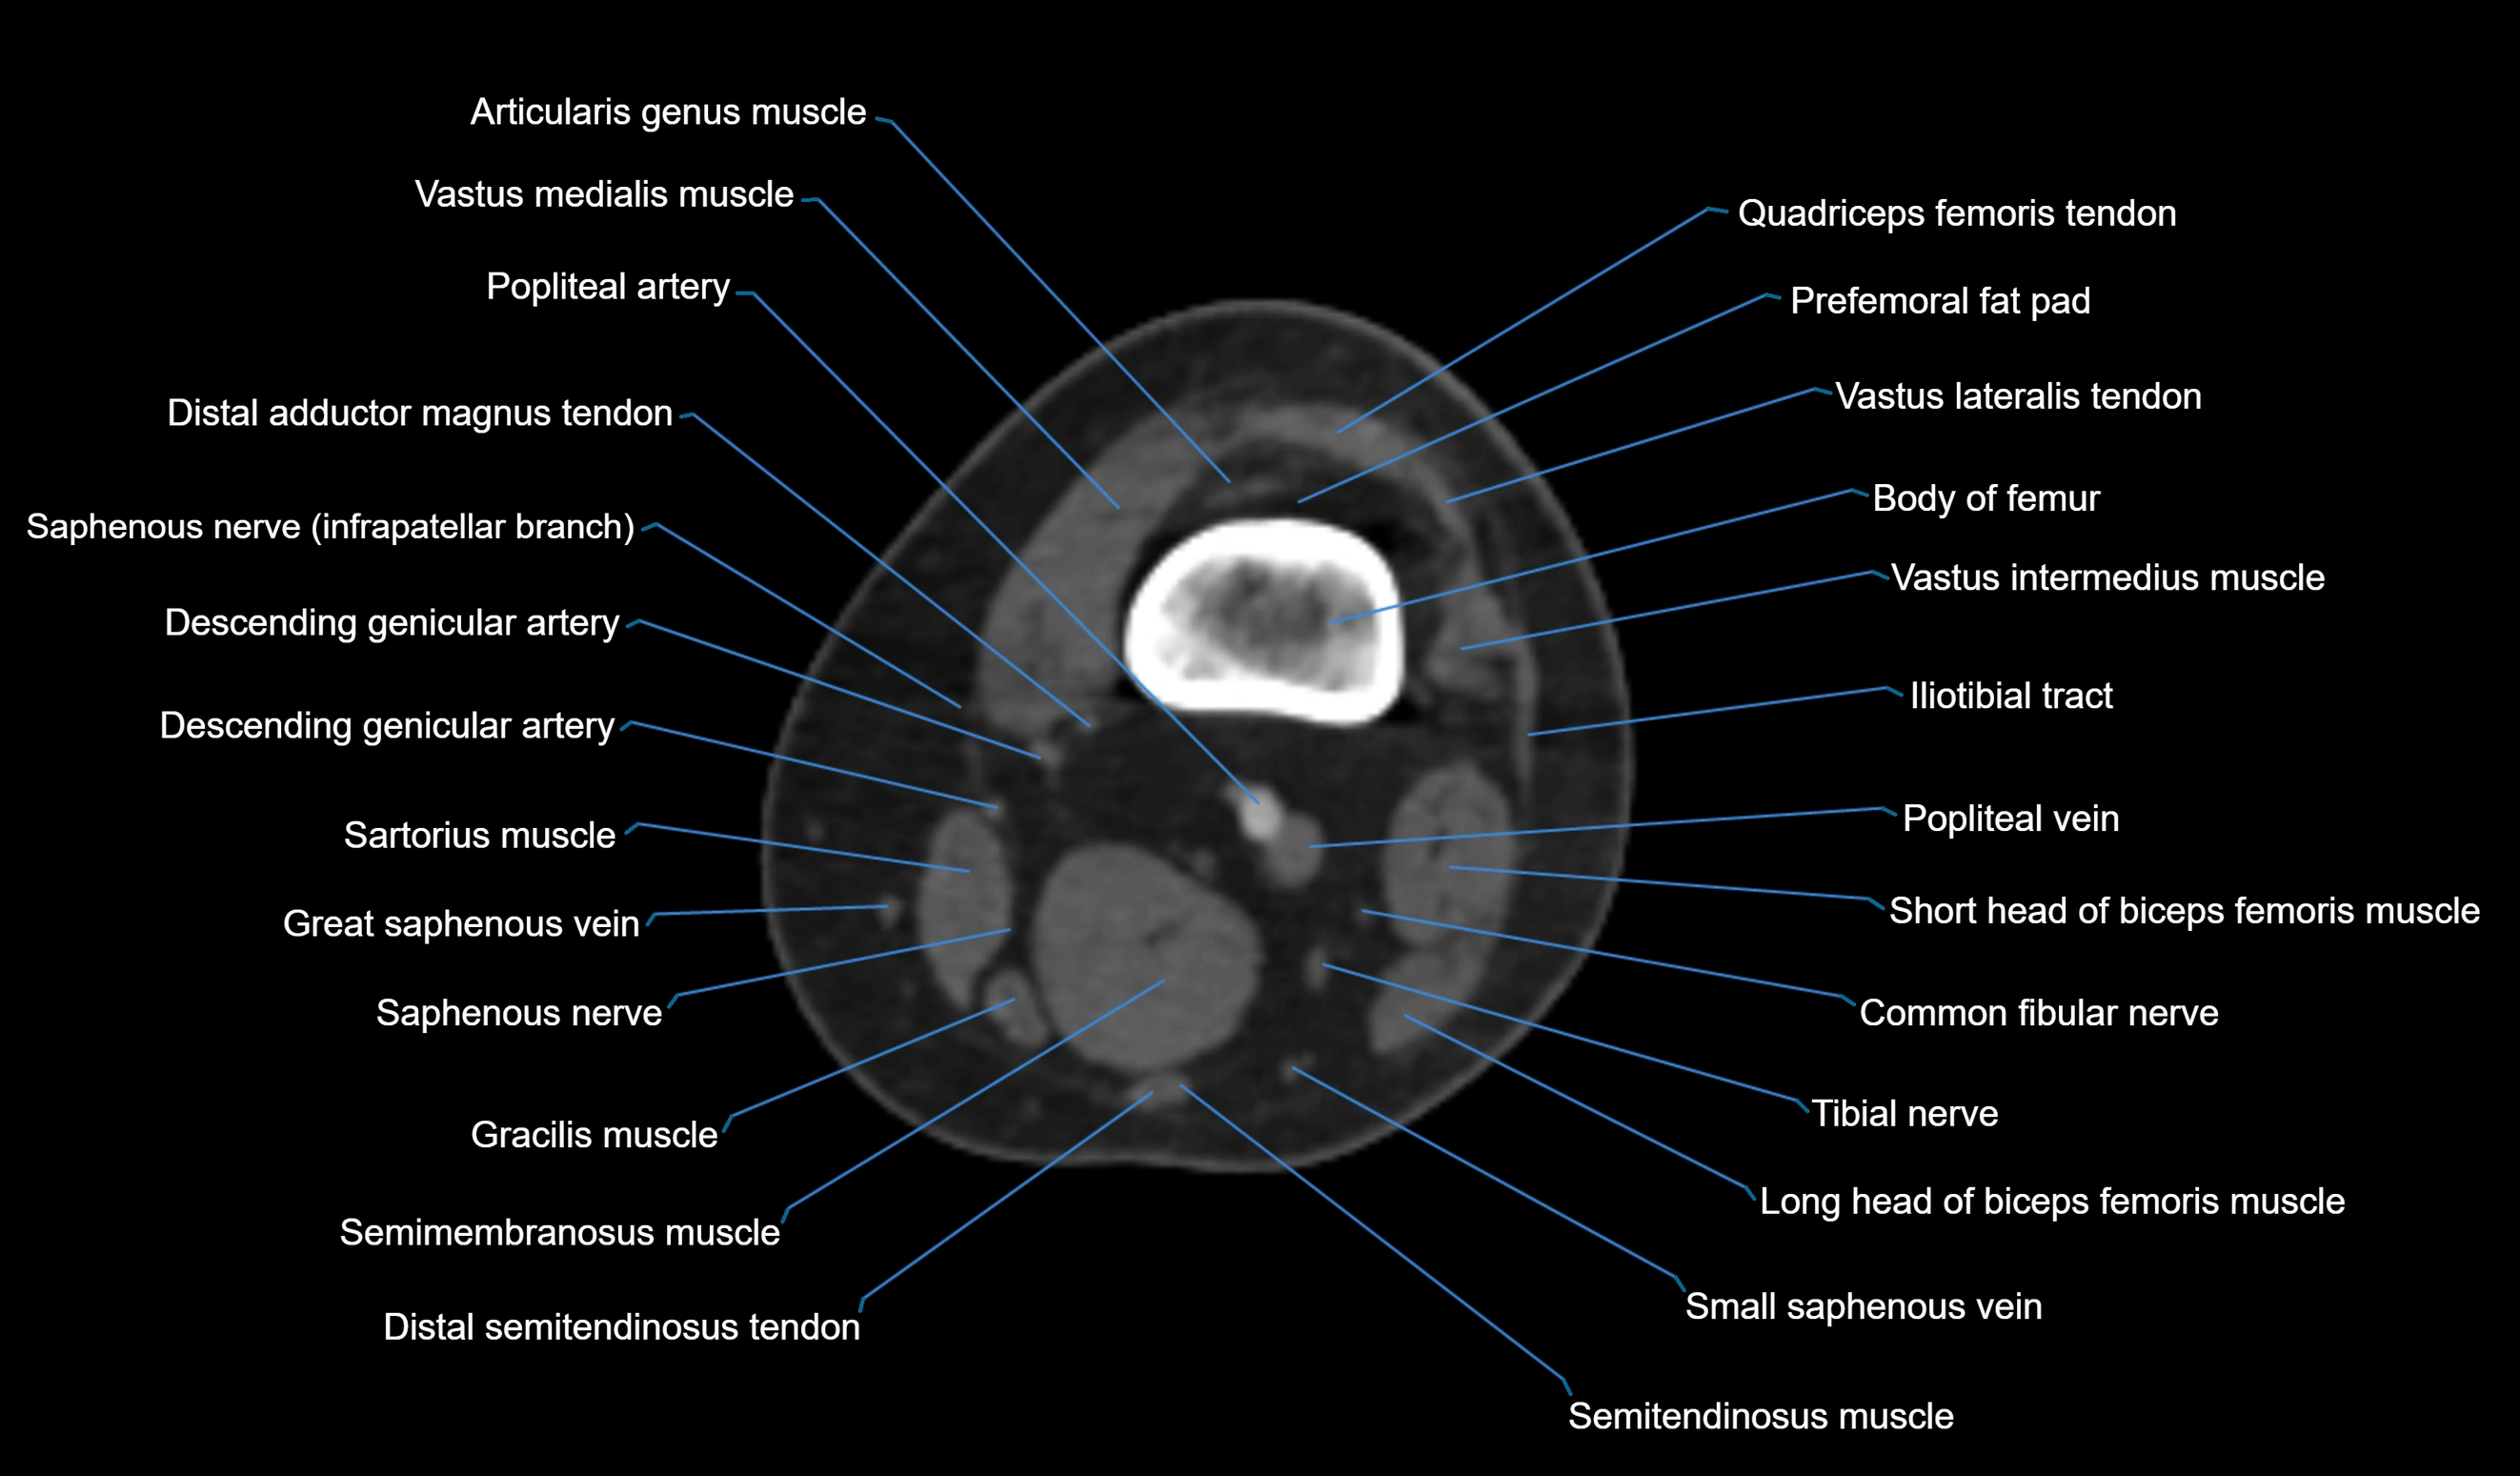

CT VRT 3D image

CT image